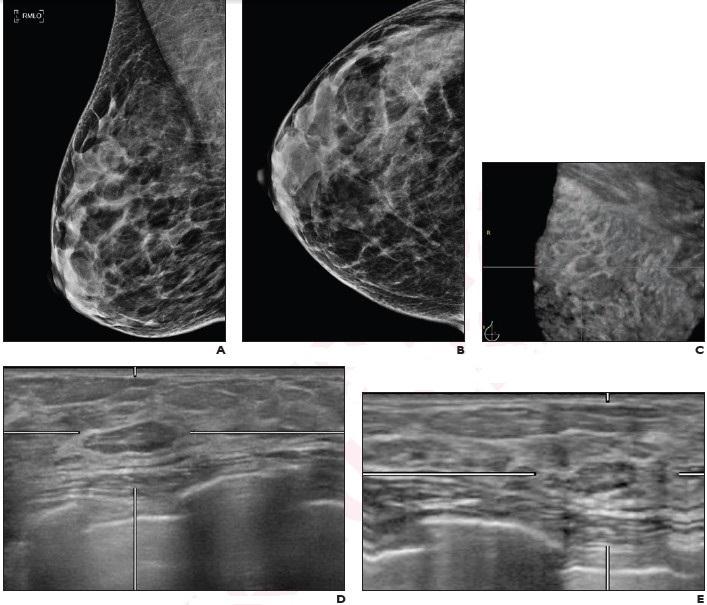

image: Normal right mediolateral oblique (A) and craniocarudal (B) view screening mammograms demonstrate density C breasts. Coronal (C), transverse (D), and reconstructed lateral (E) views from supplemental automatic breast ultrasound (ABUS) demonstrates 7 mm circumscribed slightly hypoechoic circumscribed lesion at 11 o'clock position in right breast. Lesion was classified as BI-RADS 3. Patient has undergone yearly mammograms for 4 years following the ABUS examination with no breast cancer diagnosis.